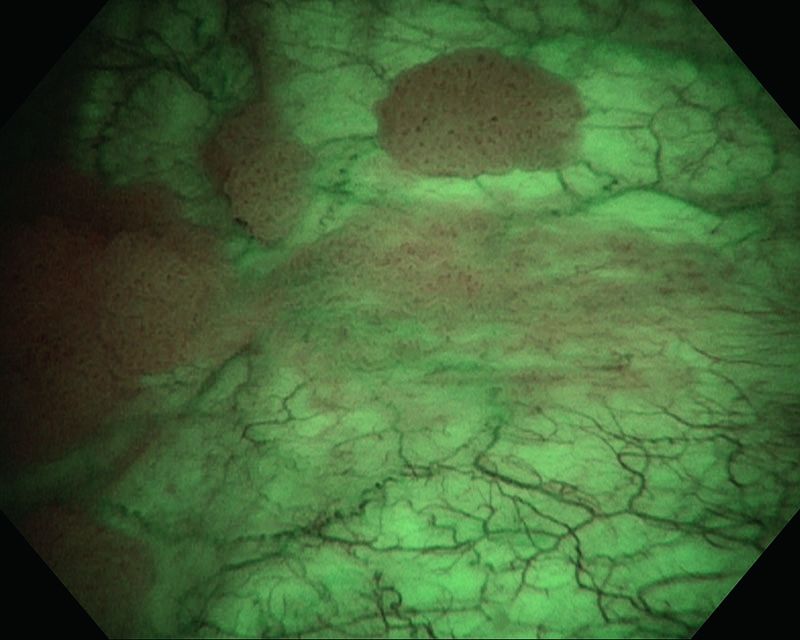

Tumor peduncular papilar, homem de 82 anos

Luz branca

NBI

Histologia UC, pTa, Low grade(G2)

Comentários

O uso da NBI nos permitiu visualizar uma região marginal de pequenos tumores que eram difíceis de visualizar sob a luz branca.